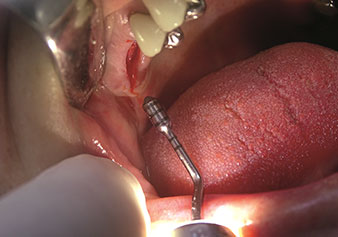

Rialzo del seno interno

W&H offre, inoltre, la soluzione perfetta per il rialzo del seno interno.

Dopo la preparazione dei seni mascellari con il corrispondente set di strumenti (Fig. 3), il nuovo strumento Z35P (Fig. 4) viene utilizzato per sollevare la membrana idrodinamicamente. Lo stesso set di strumenti può essere utilizzato anche per la preparazione piezochirurgica della sede dell’impianto in diametri crescenti (Figure 3 e 4 inserite grazie alla gentile concessione del Dott. Mario Kirste, Frankfurt/Oder).